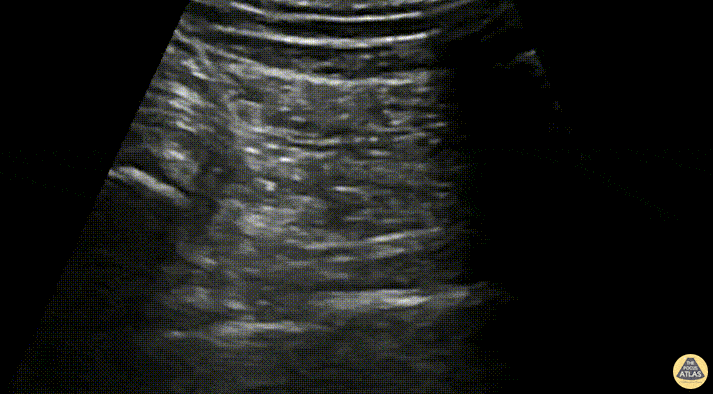

A 36-year-old male presented to the ED with acute onset left sided back pain that started suddenly 6 hours prior to arrival while bending over. The pain radiated down his left leg and he had a positive straight leg raise with a severely antalgic gait. A transgluteal sciatic nerve block was performed. The patient was positioned in the right lateral decubitus position with the left hip and knee flexed. The needle can be seen approaching from lateral to medial, just over the greater trochanter. The needle reaches the fascial plane between the gluteus maximus and quadratus femoris muscles where the sciatic nerve and inferior gluteal artery lie. The plane is seen separating with hydrodissection using 20 cc of 0.5% bupivacaine with 10 mg of dexamethasone. The patient had complete relief after the block and was able to ambulate out of the department with ease. Dr. Kate Simeon, PGY-4, Denver Health Emergency Medicine Residency Dr. Fred Milgrim, Ultrasound Fellow, Denver Health Emergency Medicine